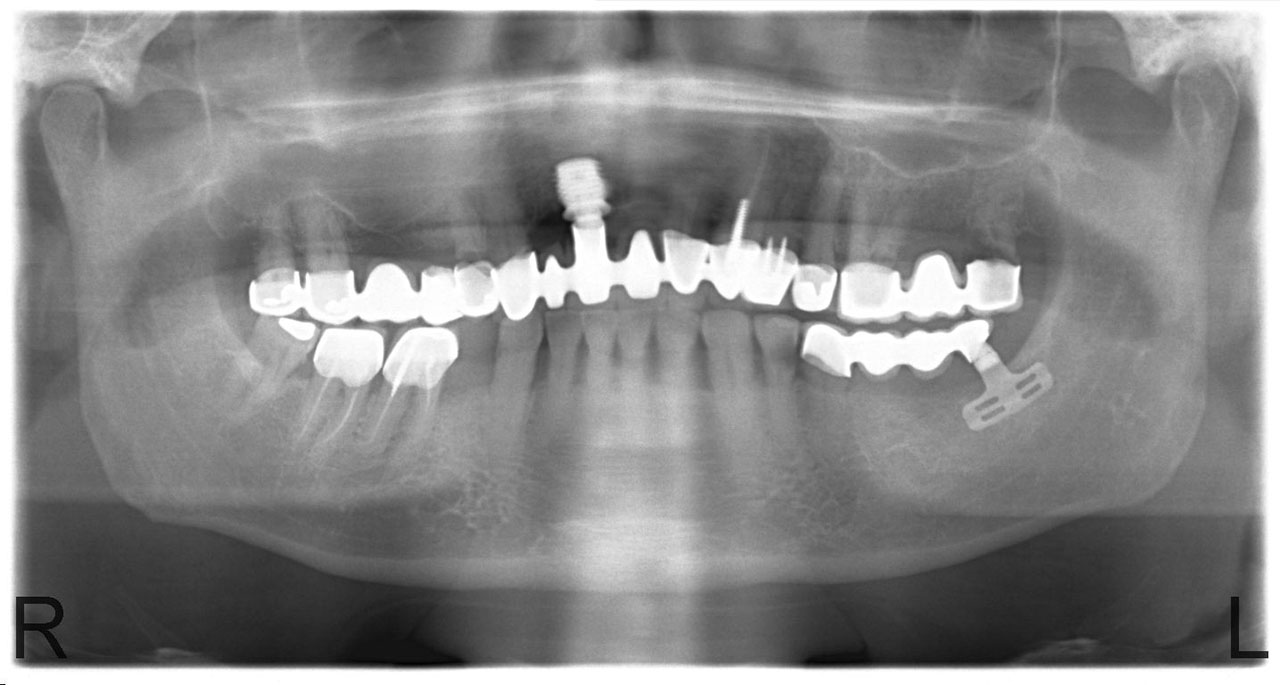

• esettanulmany-16

Mozgó műanyag híd és kiterjedt foghiány a műtét előtt.

• esettanulmany-31

72 órával az implantáció után már szájban a hosszútávú ideiglenes híd.(Fém vázzal erősített műanyag híd.)